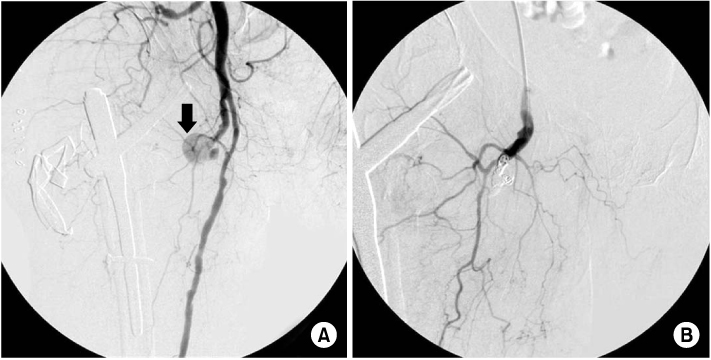

Fig. 4

(A) Digital subtraction angiography showing contrast extravasations originating from one of the minor proximal branch of right deep femoral artery, while filling a 2 cm sized pseudoaneurysm (arrow).

(B) After embolization. Postembolization angiography demonstrated no additional extravasation of contrast medium.

Fig. 4 (A) Digital subtraction angiography showing contrast extravasations originating from one of the minor proximal branch of right deep femoral artery, while filling a 2 cm sized pseudoaneurysm (arrow). (B) After embolization. Postembolization angiography demonstrated no additional extravasation of contrast medium.